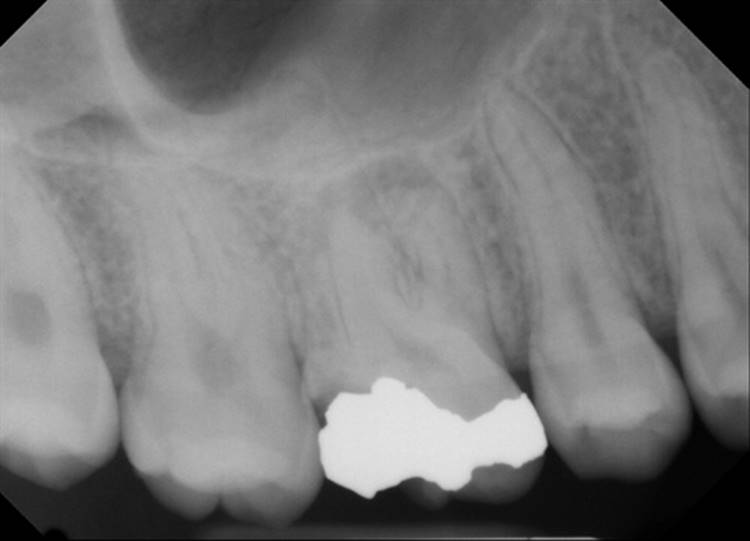

Forgive the sensor change from the first two cases to the last two. The good sensor broke and the back up isn’t as great.

EdgeFile® Cases